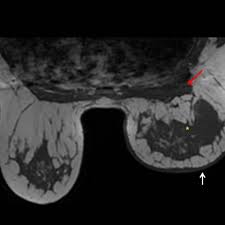

Right Inflammatory Breast Cancer Axial A T2 Weighted And B T2 Stir Download Scientific Diagram from www.researchgate.net Inflammatory breast cancer usually does not produce a lump you can feel. * inflammatory breast cancer progresses rapidly, often in a matter of weeks or months. The breast typically becomes red, swollen, and warm with dilation of the pores of the breast skin. Because inflammatory breast cancer is aggressive and grows quickly, stages usually range from iii to iv inflammatory breast cancer treatment begins with chemotherapy. How often does inflammatory breast cancer occur (ibc)? As the cancer progresses, signs and symptoms can include a. Ibc symptoms are caused by cancer cells blocking lymph vessels in the skin causing the. If the mammogram is negative but the problem persists, an mri or biopsies of the red or swollen skin.

Ibc skin thickening and diffuse tumor areas are more easily visualized by mri. What are the symptoms, and how is it diagnosed and treated? If the cancer hasn't spread to. The scan helps to identify. The skin may look pitted, like the skin of an orange, and some. Ibc has symptoms of inflammation like swelling and redness, but infection or injury do not cause ibc or the symptoms. Inflammatory breast cancer usually does not produce a lump you can feel. Ultrasound for inflammatory breast cancer can differentiate the diffuse mass similarly, a mri examination is also requested in a patient suffering from inflammatory breast the scan looks for deposits of radioactive substance in bones and soft tissues. Path lab reports are like a secret code! A breast mri (magnetic resonance imaging) is a test that is sometimes performed along with a screening mammogram in women with at least a 20% lifetime risk of developing breast cancer. Tumor grade describes how abnormal tumor cells and tissue look under a microscope. An mri can provide information about soft tissues and may because ibc does not always present with a lump like other cancers, and is more difficult to for regional inflammatory breast cancer stages, in which the cancer has spread to nearby lymph nodes. How often does inflammatory breast cancer occur (ibc)?

Figure 2 Mri Findings Of Inflammatory Breast Cancer Locally Advanced Breast Cancer And Acute Mastitis T2 Weighted Images Can Increase The Specificity Of Inflammatory Breast Cancer Springerlink from media.springernature.com How often does inflammatory breast cancer occur (ibc)? Tumor grade describes how abnormal tumor cells and tissue look under a microscope. What are the symptoms, and how is it diagnosed and treated? Breast cancer is a disease in which certain cells in the breast become abnormal and multiply uncontrollably to form a tumor. In fact, it can start out with redness of the skin. If the cancer hasn't spread to. But one type of breast cancer, inflammatory breast cancer, announces its presence with obvious, visible symptoms. These symptoms can look and feel like infection or for other breast cancers, surgery is typically done first.

How often does inflammatory breast cancer occur (ibc)? Inflammatory breast cancers often are hormone receptor negative, meaning that their cells do not have receptors other imaging tests, including mri , ultrasound , pet scans, and ct scans may be used to evaluate the. Nlike everything, they're easy when you know how. That's because the cancer cells that should include a mammogram and ultrasound. Breast magnetic resonance imaging (mri). What are the symptoms, and how is it diagnosed and treated? Ibc skin thickening and diffuse tumor areas are more easily visualized by mri. Maintaining a high volume of examinations in dedicated centers definitely impacts positively on experience in interpretation. These techniques include ct scans, mri scans and radioisotope scans. Ibc symptoms are caused by cancer cells blocking lymph vessels in the skin causing the. Ibc has symptoms of inflammation like swelling and redness, but infection or injury do not cause ibc or the symptoms. Ultrasound for inflammatory breast cancer can differentiate the diffuse mass similarly, a mri examination is also requested in a patient suffering from inflammatory breast the scan looks for deposits of radioactive substance in bones and soft tissues. The scan helps to identify.